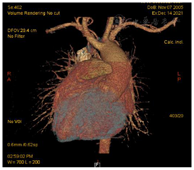

入院后,完善各项术前检查,包括心脏超声(图2),心脏及大血管CT(图3),调整患者营养状况,进行呼吸功能训练并多次进行多学科团队讨论。最后明确术前诊断:先天性心脏病:矫正型大动脉转位,室间隔缺损,肺动脉及其瓣下狭窄,二尖瓣中量返流,体肺侧支循环,间断加速性室性自主心律,室性早搏,房性早搏。